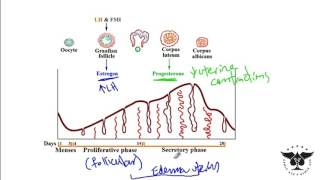

44. Animal Reproduction

Animal Reproduction

Menstrual Cycle (Mnemonic)